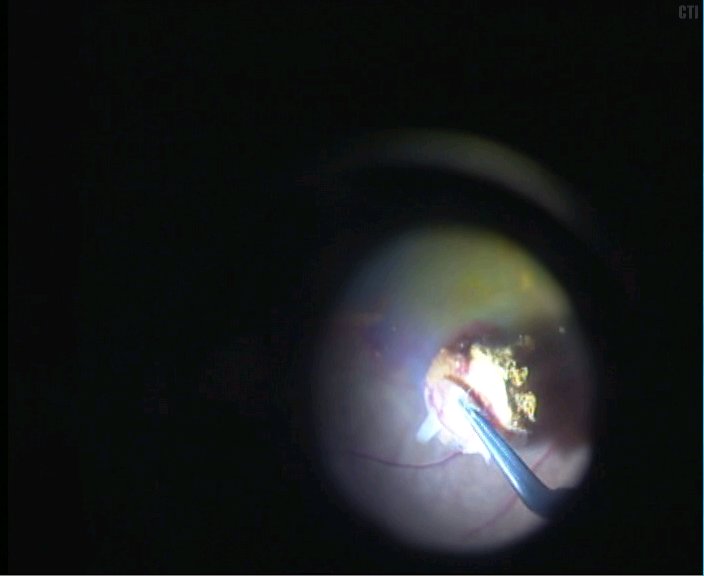

1、术前可见黄斑下血管膜机化渗出

2、黄斑区下方剪开视网膜

3、局部注水视网膜脱离后取出黄斑下机化的新生血管膜

4、取出机化膜可见黄斑区下大片的色素上皮缺损